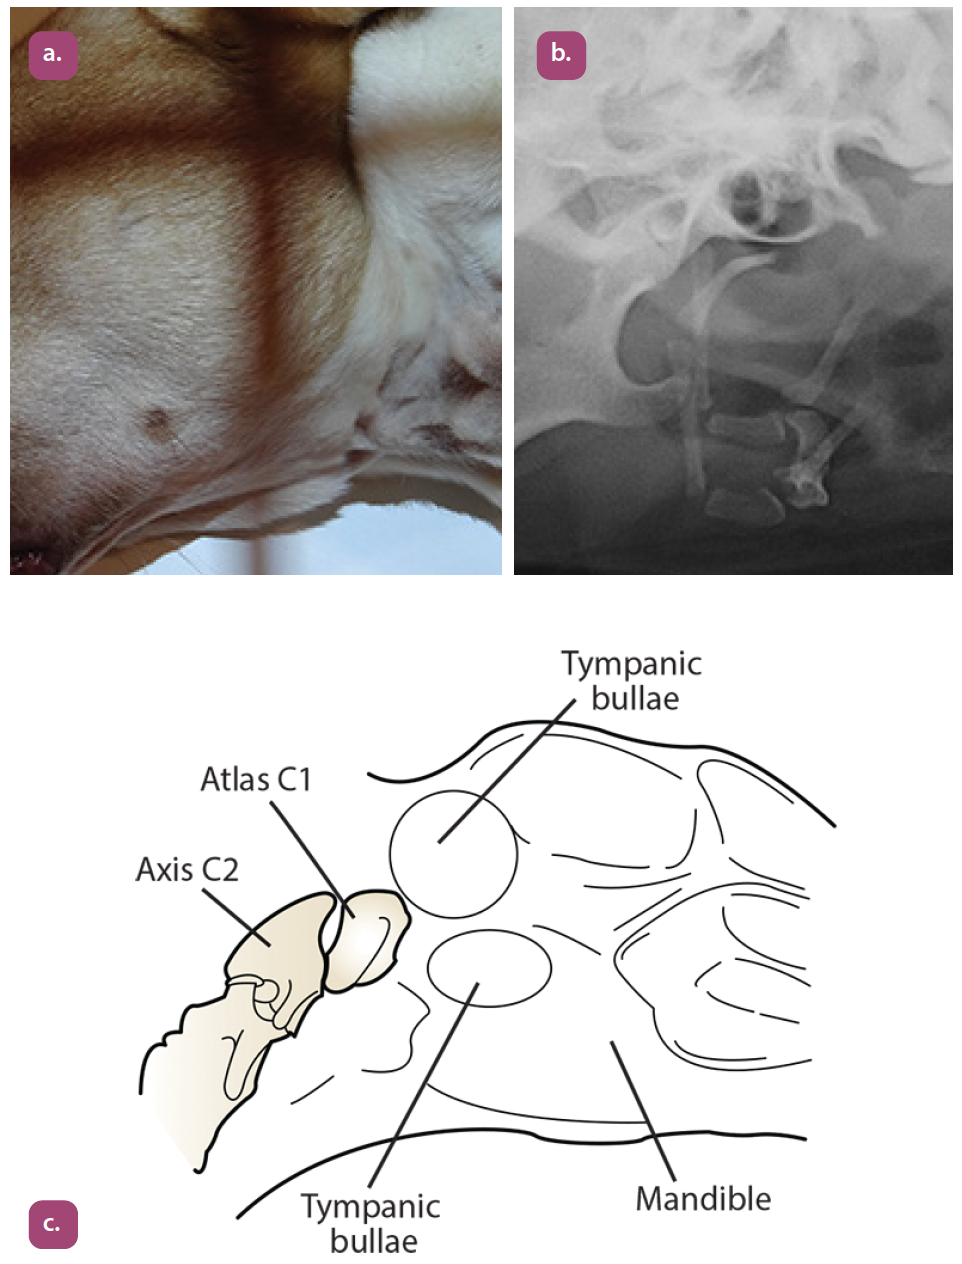

lateral oblique tympanic bullae projection